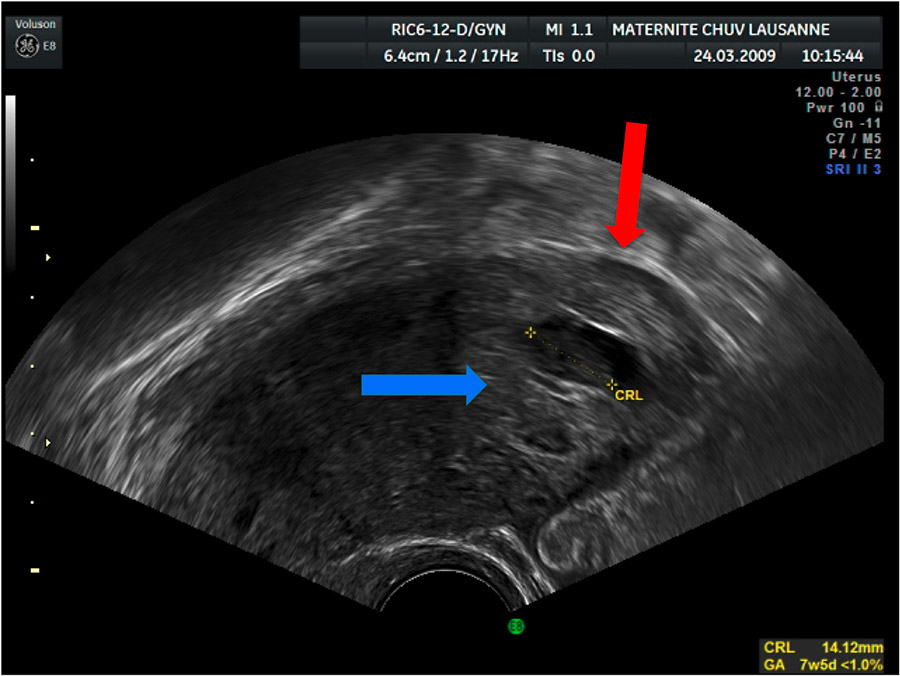

Figure 1

TVUS sagittal image showing an eccentric GS, blue arrow, surrounded by a thin myometrial layer, red arrow.

1 an eccentric gestational sac (GS) in regard to the uterus in a sagittal axis (fig. 1);

3 less than 5 mm of myometrial layer around the GS (fig. 1);